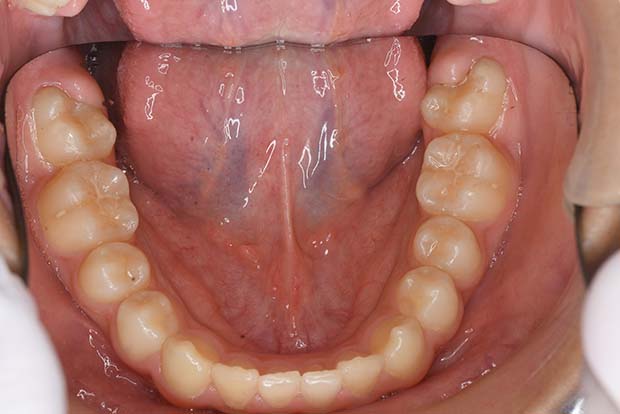

【空隙歯列】非抜歯 舌側マルチブラケット装置

| 主訴 |

すきっ歯 |

||

|---|---|---|---|

| 診断名 |

左側Angle III級空隙歯列 |

||

| 年齢 | 47歳 | 性別 | 男性 |

| 治療に用 いた装置 |

舌側マルチブラケット装置(セミカスタム) | 抜歯部位 | 非抜歯 |

| 治療期間 ・回数 |

1年6か月・18回 | 治療費 概算 |

約75万円 (調整料を含む) |

| 治療内容 詳細 |

すきっ歯を非抜歯で治療した症例です。上下とも舌側矯正(裏側矯正)で治療しています。 |

||

| リスク・ 副作用 |

装置による違和感。疼痛など |

||